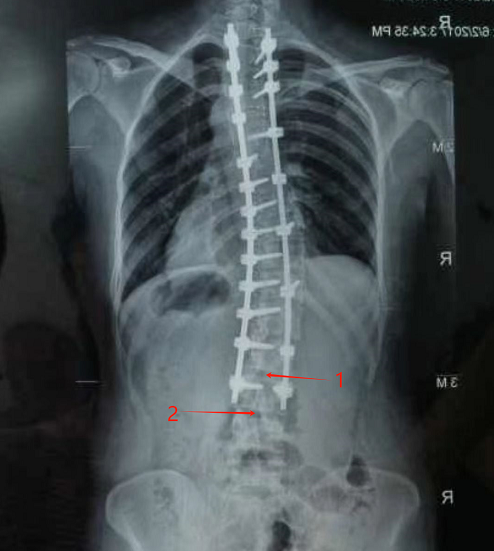

“是不是这里可以打进去?”吴强有了这样的想法。据悉,普通患者进行腰麻,一般选择腰2-3或腰3-4处为麻醉穿刺点,而薛女士的腰2-3及以上的部位都被钢钉牢牢固定,只有腰3-4可以一试。

标记1是腰2-3间隙,标记2是腰3-4间隙,也是本次麻醉穿刺的位置。